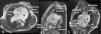

A 39-year-old female with long term idiopathic pulmonary arterial hypertension (PAH), under triple pulmonary vasodilator therapy, was evaluated at our Pulmonary Hypertension Unit. Due to lack of recent imaging assessment, a transthoracic echocardiogram and a cardiac magnetic resonance were performed. They revealed right heart dilatation, severely dilated pulmonary artery branches and an aneurysmatic pulmonary trunk, measuring 71 mm along its longer axis (Figure 1A–C). Although risk stratification was low according to the European Society of Cardiology guidelines, the patient was referred for pulmonary transplant. Massive (>50 mm) pulmonary artery aneurysms (PAA) are extremely rare.1 Their presence in PAH requires exclusion of schistosomiasis (excluded) or associated congenital heart disease.2 A previously undiagnosed anomalous drainage of a pulmonary vein into the superior vena cava was detected in this patient. Whether this had a role in the development of PAH remains unclear. Given the risk of dissection, rupture or compression of coronary arteries, pulmonary transplant referral is advised.2